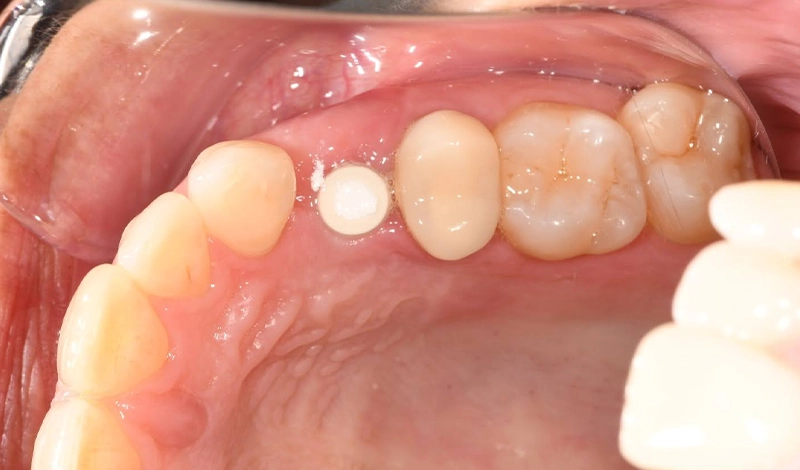

Gabby’s outcome

Following treatment, the clinical objectives were achieved as planned:

- The missing upper left first premolar was replaced with an implant and crown, supported by a soft-tissue graft.

- The grafted gum at the site demonstrates stable contour on review.

- The upper left second premolar has been restored with a porcelain crown.